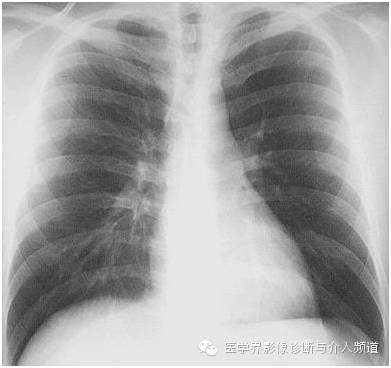

22岁年轻男性,发热38°C,踝关节疼痛伴红斑结节。

很多时候只给一张胸片,你能看出上图异常吗?

异常:双肺门淋巴结肿大。

到这里一张胸片中观察到的异常就结束了,再结合非常重要的临床病史,你得想到这个病–结节病,本病例为急性结节病。